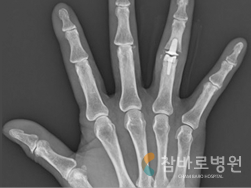

4. 손가락 인공 관절 수술

· 심한 류마티스 관절염으로 손가락 변형이

생기고 움직일 수 없는 상태

· 인공 관절 치환술로 변형이 교정되고

정상생활이 가능한 상태